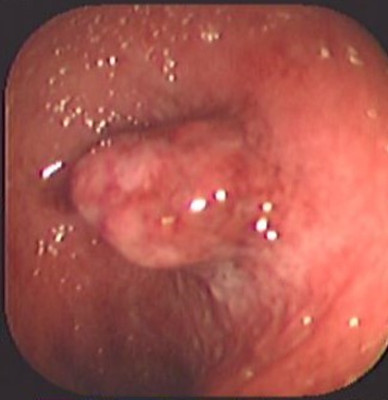

Colitis ulcerosa crónica inespecífica

Envíado por Dr. Carlos Ernesto Arévalo